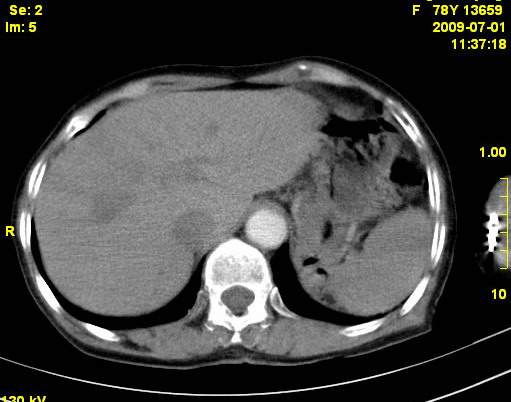

以下是引用zjzjr在2009-7-3 11:02:00的发言:[br]动脉期不均匀强化,门脉期及延迟期强化明显,肝门部见肿大淋巴结影,肝内胆管扩张.考虑肝右叶前段胆管细胞癌伴肝门淋巴结转移,胆内胆管扩张.慢性胆囊炎.

以下是引用dsl555在2009-7-4 10:59:00的发言:[br]考虑肝右叶前段胆管细胞癌伴肝门淋巴结转移,胆内胆管扩张.慢性胆囊炎. [br][br]支持。